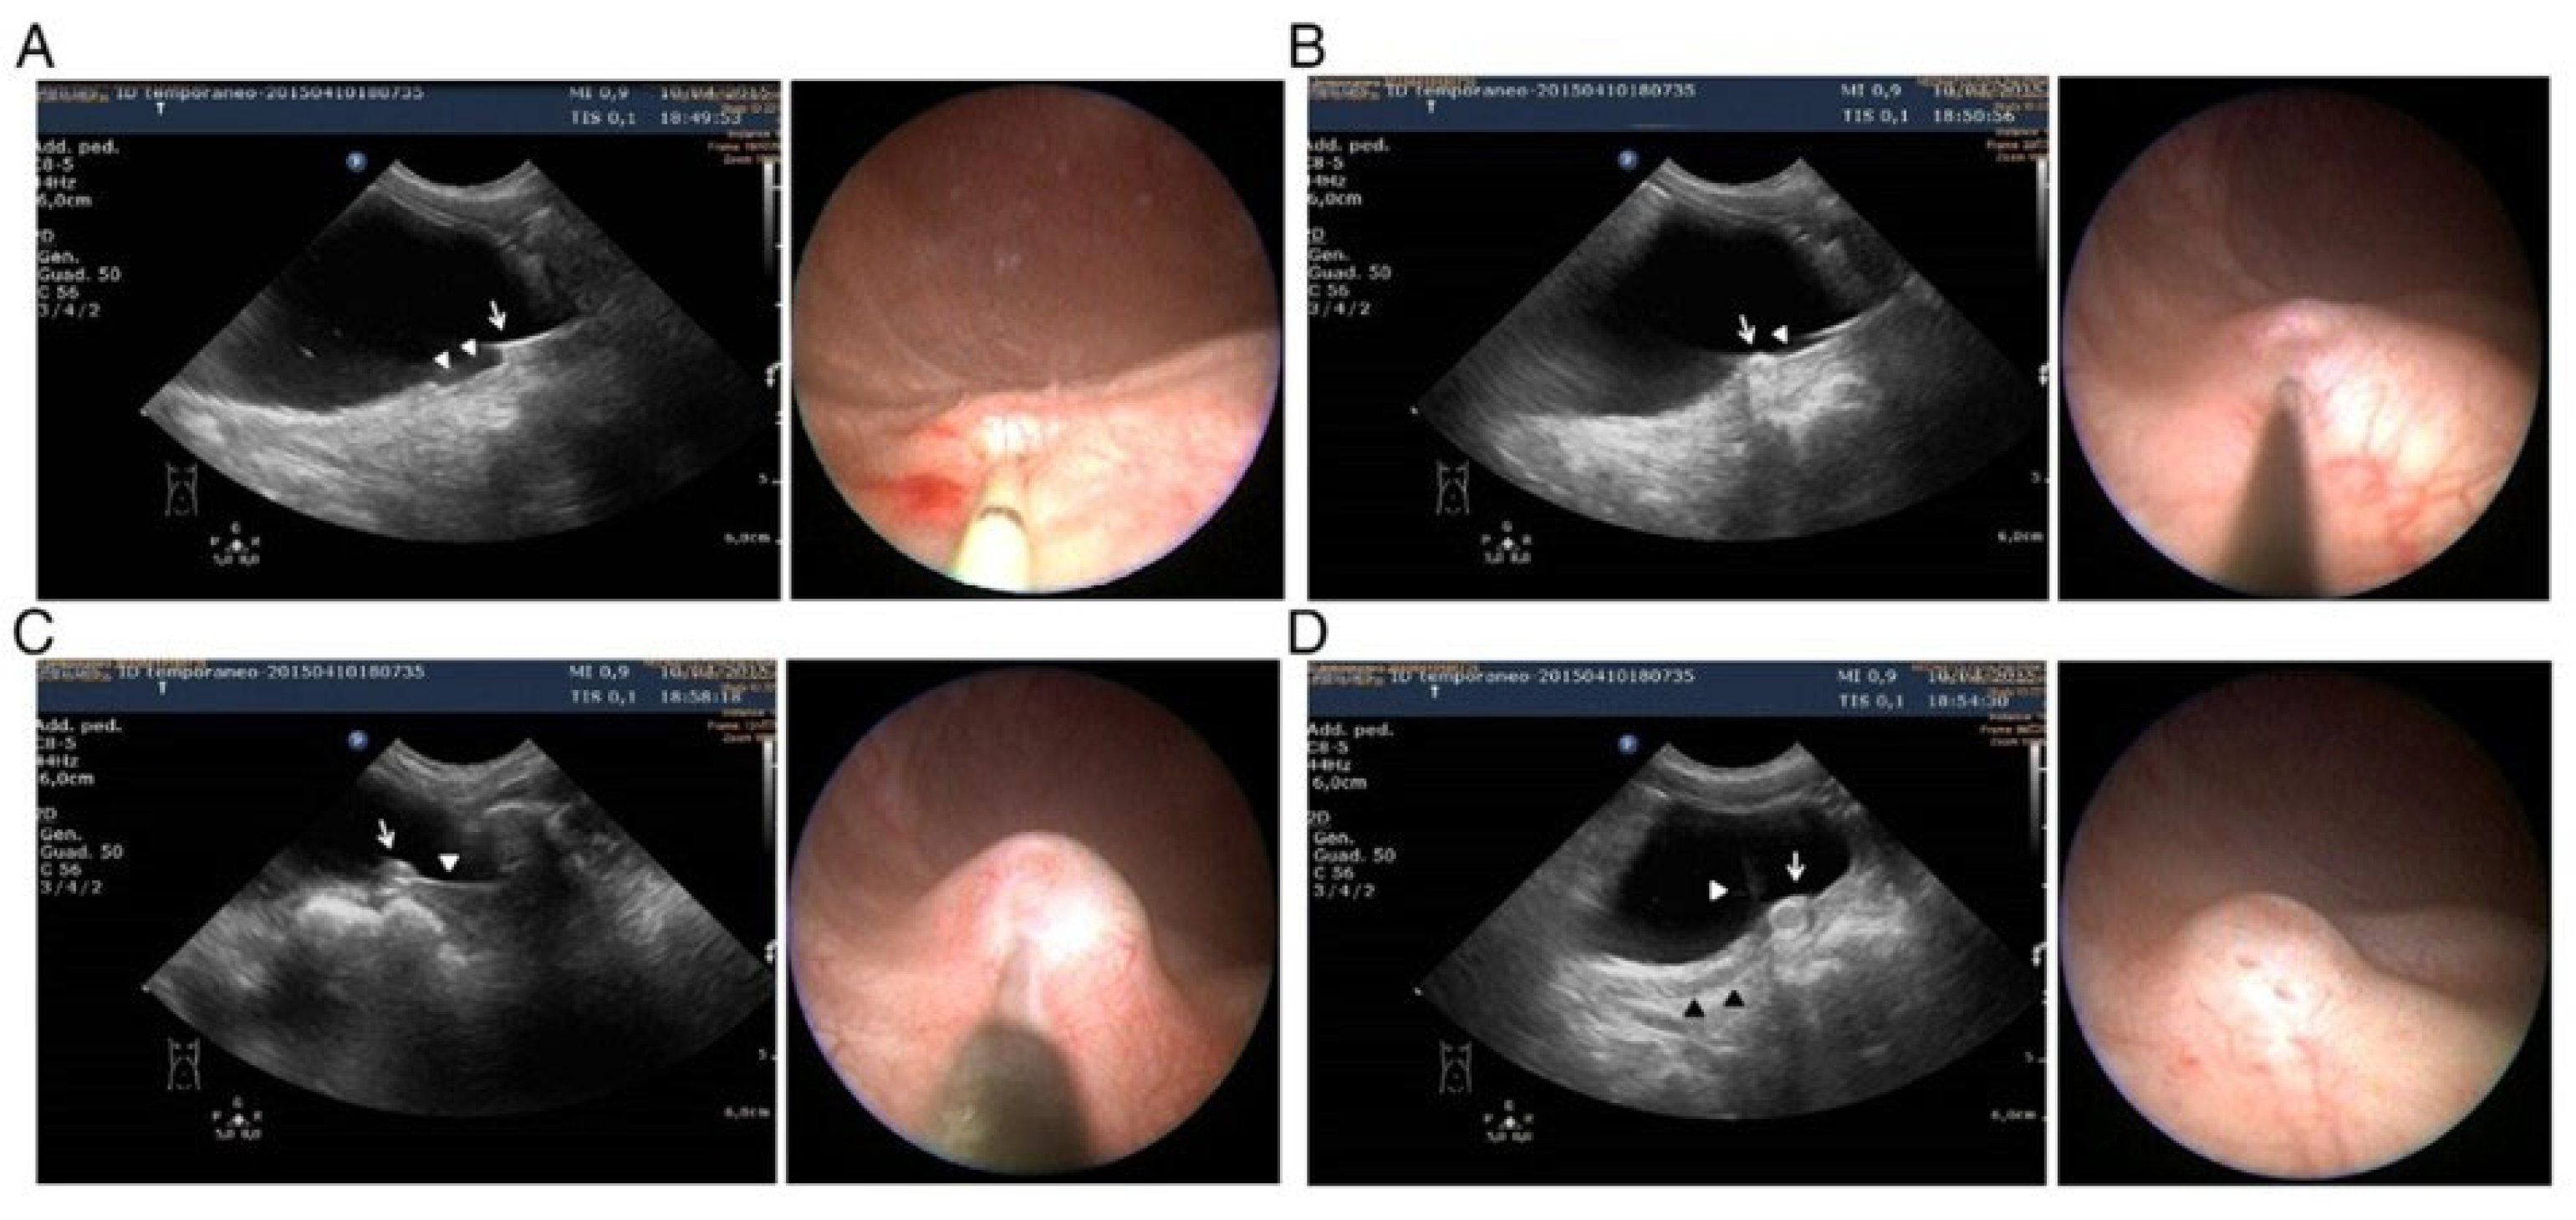

- Zambaiti, E.; Sergio, M.; Casuccio, A.; Salerno, S.; Cimador, M. Intraoperative ultrasound-assisted approach for endoscopic treatment of vesicoureteral reflux in children. J. Pediatr. Surg. 2017, 52, 1661–1665. [Google Scholar] [CrossRef] [PubMed]

- Pensabene, M.; Cimador, M.; Spataro, B.; Serra, G.; Baldanza, F.; Grasso, F.; Corsello, G.; Salerno, S.; Di Pace, M.R.; Sergio, M. Intraoperative ultrasound-assisted endoscopic treatment of primary intermediate and high-grade vesicoureteral reflux in children in a long-term follow-up. J. Pediatr. Urol. 2024, 20, 132.e1–132.e11. [Google Scholar] [CrossRef] [PubMed]